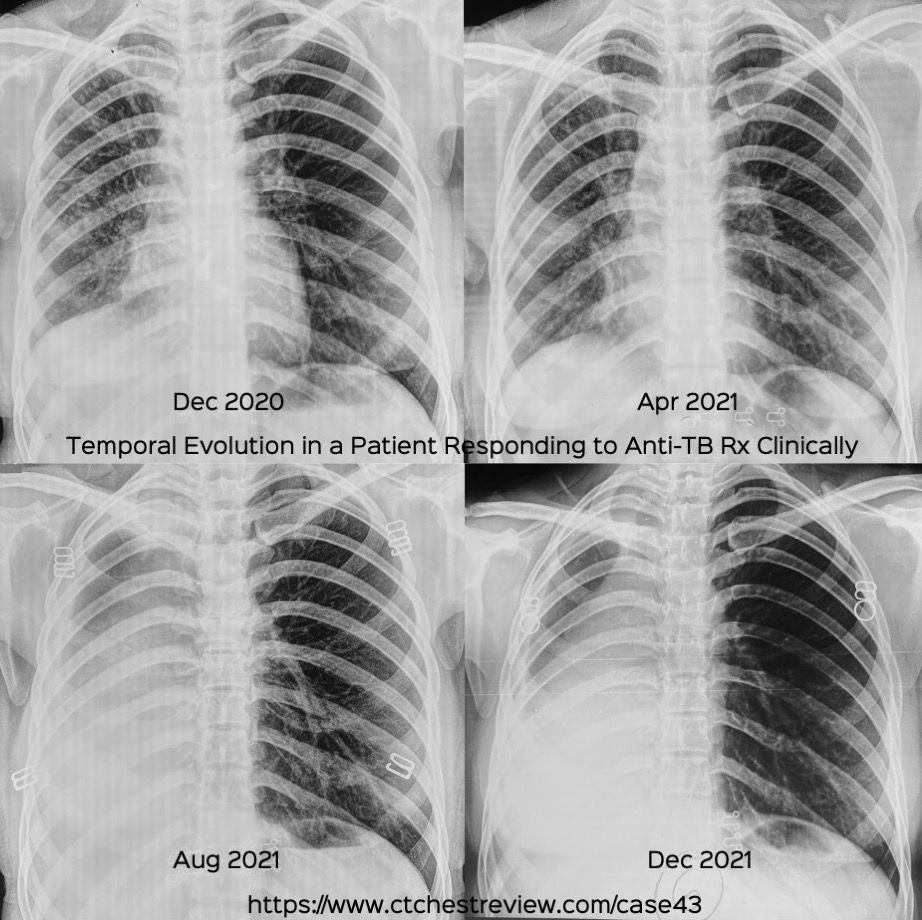

Case 43: Progressive Collapse in Patient Responding Clinically to Anti-Tuberculous Treatment Members Public

Progressive Collapse in Patient Responding Clinically to Anti-Tuberculous Treatment